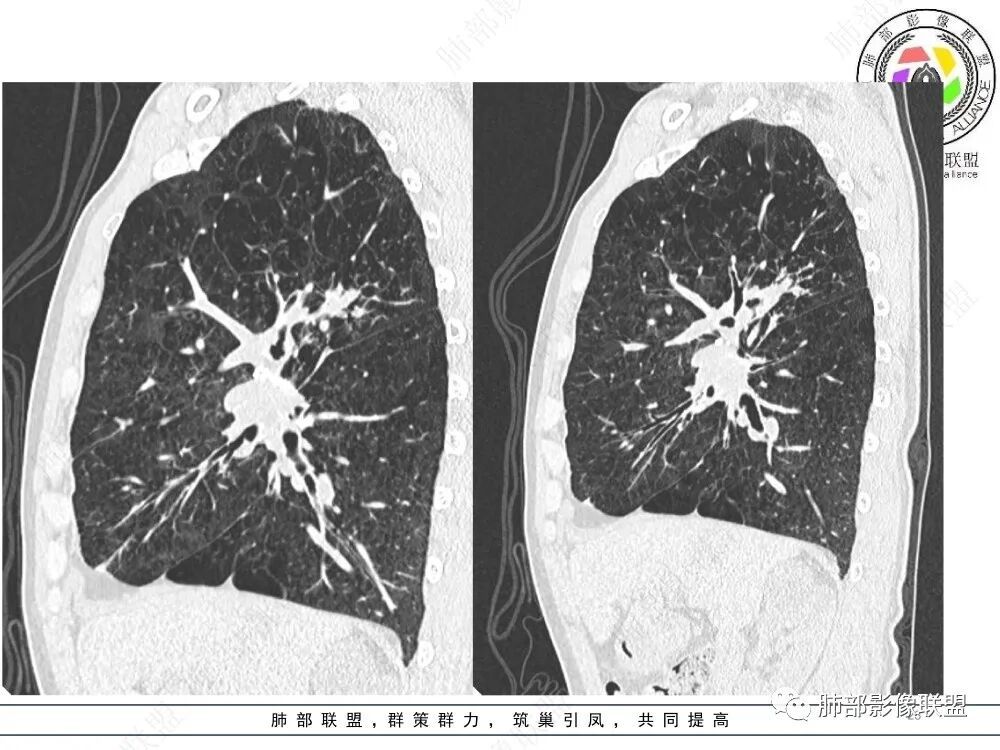

ABPA影像:1、中心型支气管扩张,常常双侧较对称,一般以段、亚段为主,支气管壁增厚,腔内有粘液栓,呈指套状或牙膏状影,粘液栓高密度(约30%),无强化。2、小气道异常∶小叶中心细支气管扩张并充有粘液——树芽征。3、伴随征象∶肺内斑片状、结节状高密度影,呈游走性;扩张支气管远端可伴有阻塞性肺气肿、肺不张,肺纤维化、局部胸膜增厚或积液。4、治疗好转粘液栓消失,扩张支气管的转归∶ 部分不变化,部分较前稍缩小,很少一部分可以恢复正常,一般壁稍增厚。

上图,ABPA,支气管扩张、腔内指套样粘液栓,部分粘液栓呈高密度,较具特征性。

上图,支气管结核。病灶多灶性、多态性。支气管中近端受累,支气管壁增厚不均匀,狭窄后扩张,伴随树芽征、钙化。